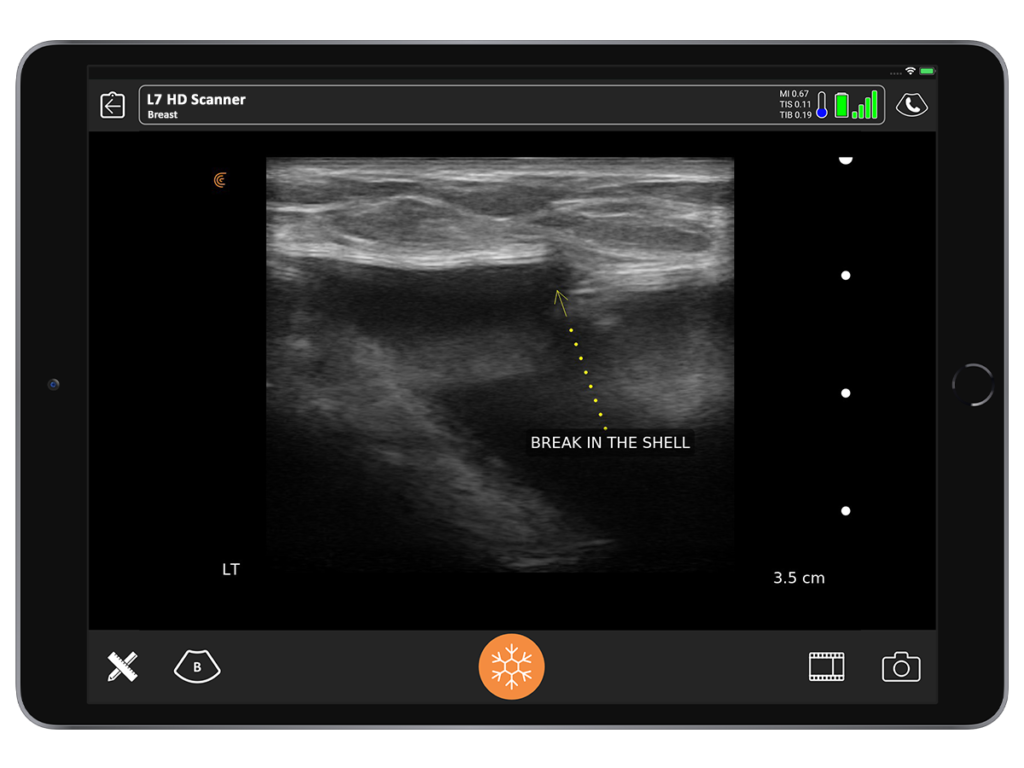

If an aspiration is needed, for example, I can do it in the office instead of waiting for someone else to do it. By using ultrasound, I’m able to say with a good degree of certainty whether an implant is broken or not. I’ve never seen a false negative.

I have seen zero surprises in the operating room since I started using ultrasound to screen patients before cosmetic surgery.

I have never encountered a broken breast implant that I didn’t know about. I’m therefore always prepared with the right replacement implant during surgery.